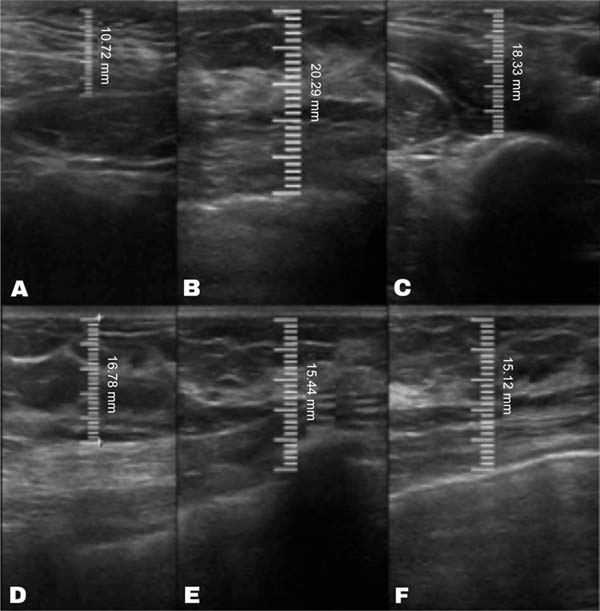

The average volume of fat grafted was 116.7 mL in the decanted graft group and 123.3 mL in the filtered graft group. The average initial thickness of the subcutaneous tissue was approximately 11 mm in both groups. This value increased to 22 mm in the immediate postoperative period in the decanted group and 23 mm in the filtered group.

Both groups presented progressive reabsorption. ►Table 1 and ►Fig. 5 show the change in mean subcutaneous thickness in both groups.

In the decanted graft group, the average reduction compared with the initial thickness after lipofilling was 9.90% on day 15, 19.27% on month 1, 23.59% on month 3, and 26.36% on month 6. In the filtered graft group, the average reduction compared to the initial thickness after lipofilling was 7.74% on day 15, 14.85% on month 1, 20.67% on month 3, and 22.80% on month 6 (►Fig. 6). ►Figs 7–8 reveal the ultrasound change in subcutaneous tissue’s thickness before and after lipofilling. ►Figs. 9–10 show the pre-and postoperative results of one patient from each group.